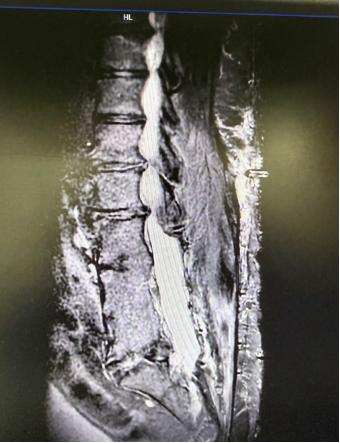

from clipboard

患者术前MRI

接诊后,疼痛科团队对患者进行了系统、全面的评估,结合其病史、临床表现及影像学检查结果,组织多学科会诊讨论。团队发现,T先生患者手术区域局部解剖结构明显异常,存在术后瘢痕粘连及椎管极度狭窄等改变,大大增加了电极置入的技术难度与操作风险。经多学科团队反复讨论并充分告知患者诊疗方案后,决定短时程脊髓电刺激作为疗效测试和安全性评估手段,后续根据镇痛效果和耐受情况,审慎评估是否行永久性电刺激系统植入,并据此制定了周密的个体化手术方案。